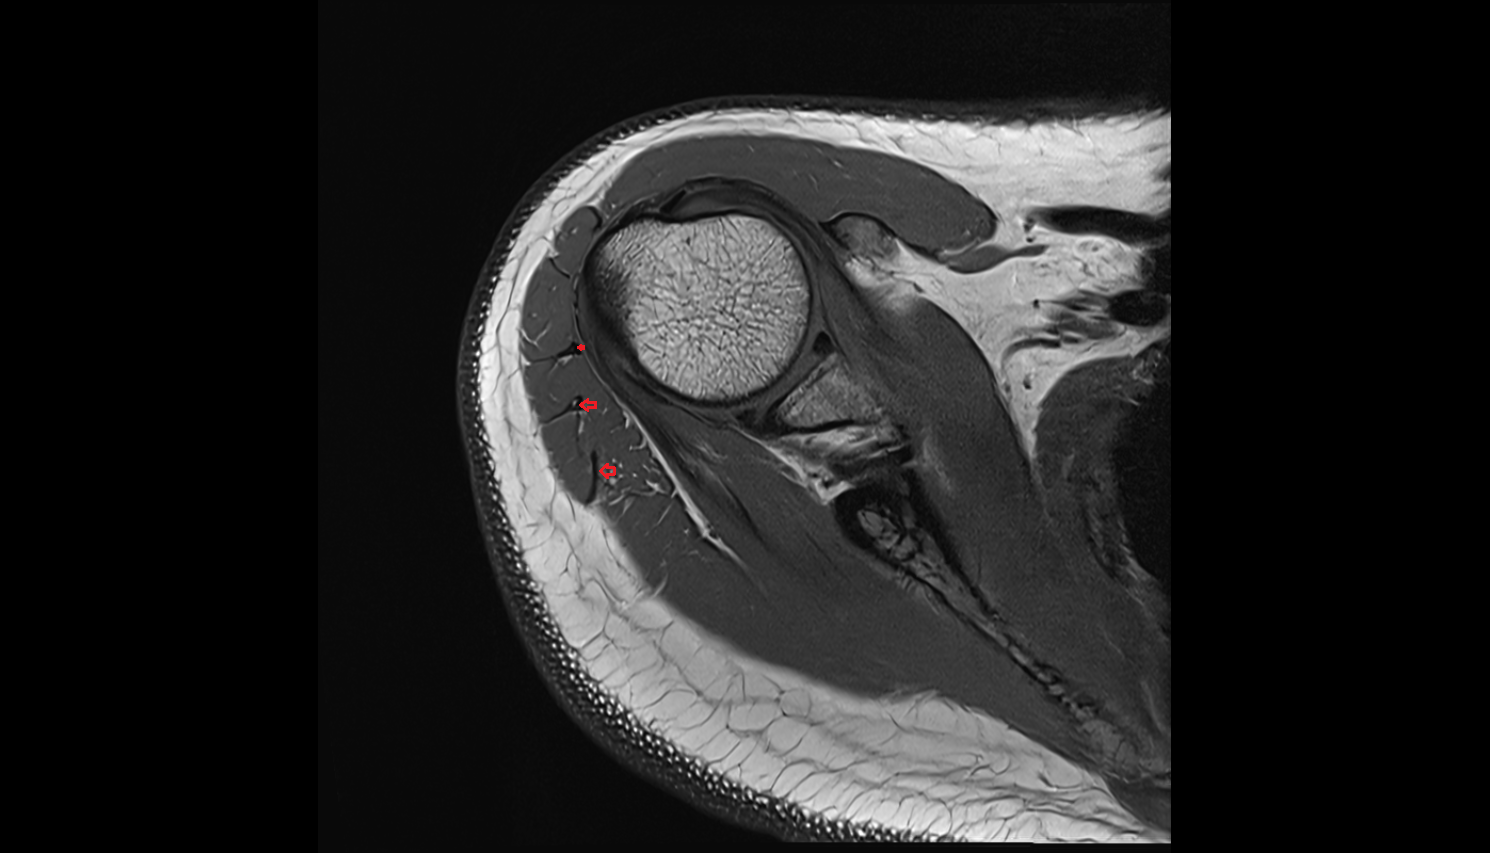

- Temporomandibular joint

- Articular disc of temporomandibular joint

- Posterior band of articular disc, TMJ

- Anterior Band of Articular Disc TMJ

- Intermediate zone of articular disc

- Superior retrodiscal layer

- Superior synovial membrane of temporomandibular joint

- Mandibular condyle

- Mandibular fossa

- Superior head of lateral pterygoid muscle

- Inferior head of lateral pterygoid muscle